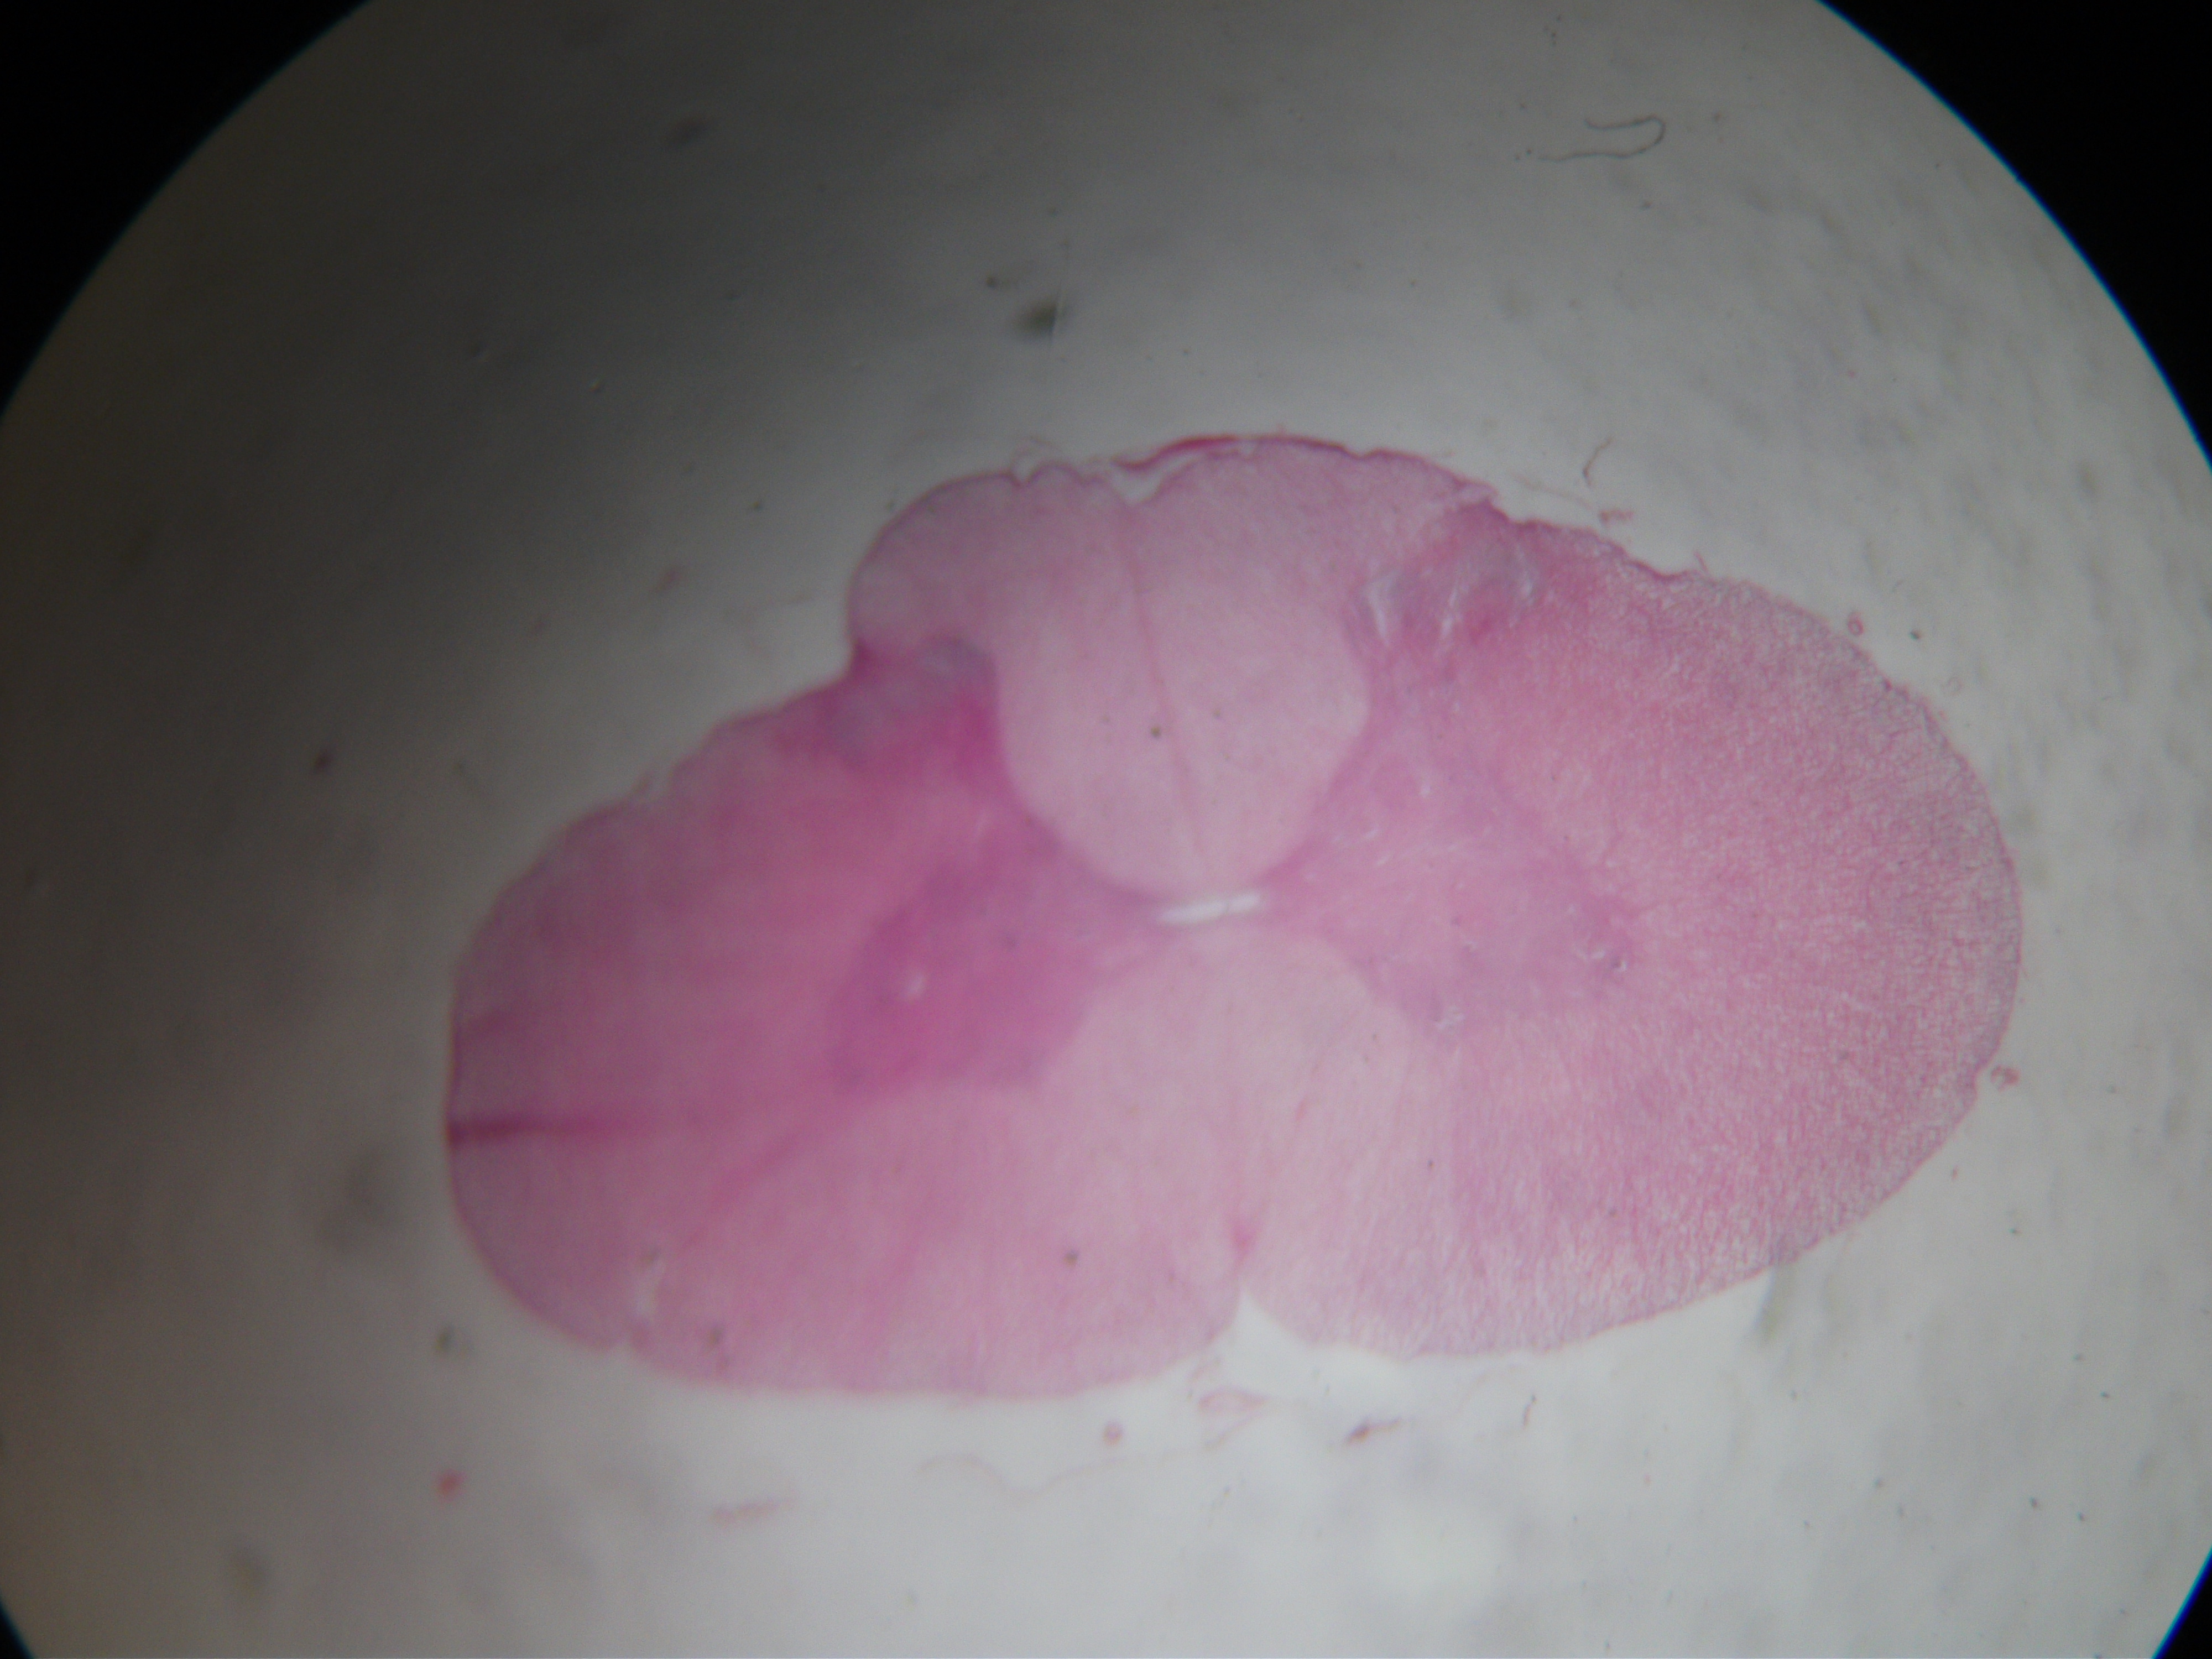

spinal cord of rabbit